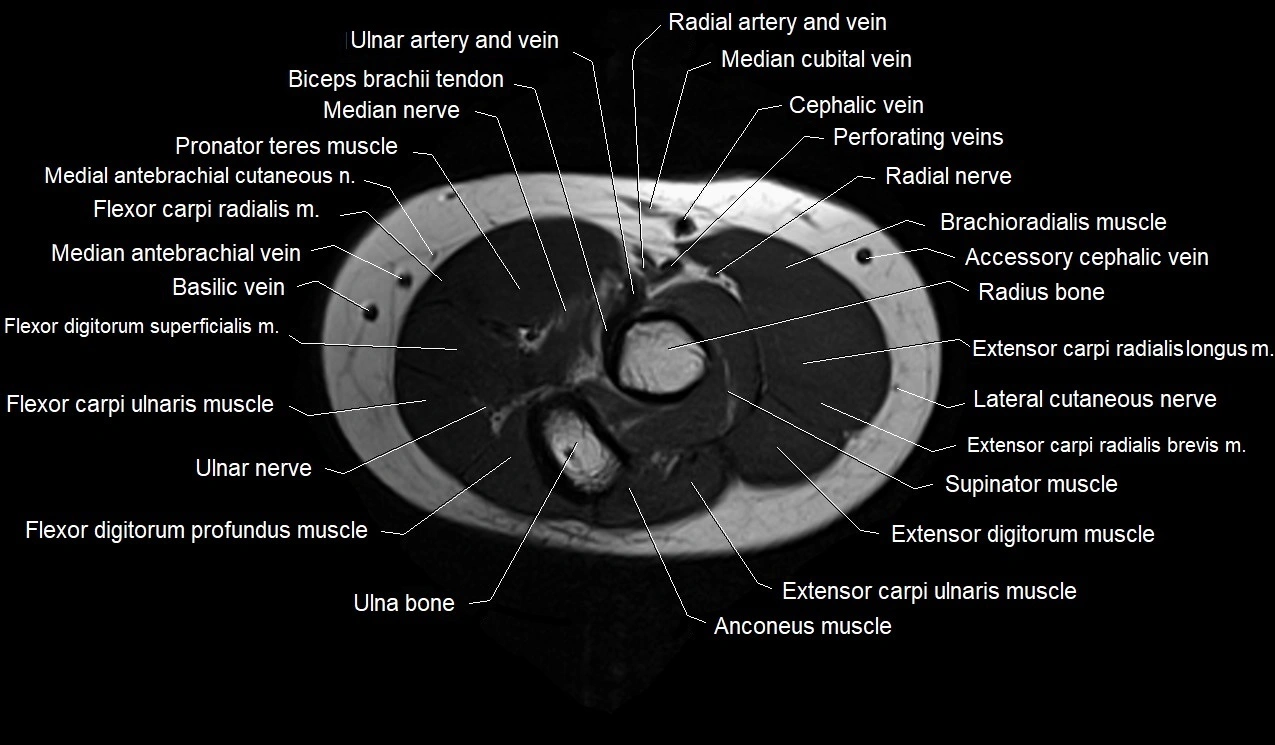

MRI images

image